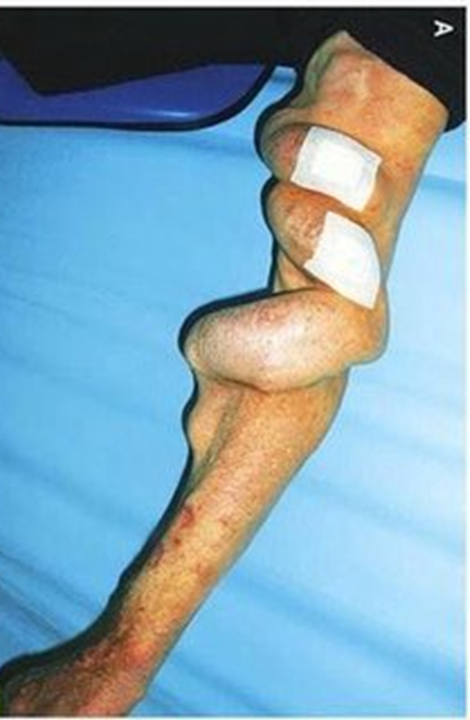

静脉曲张:肢体青筋暴露,甚至瘙痒、发黑、破溃、静脉炎症等。